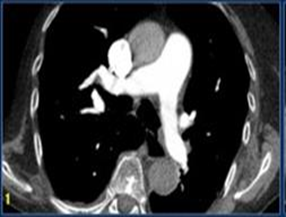

Những năm vừa qua được sự quan tâm của thủ trưởng các cấp cùng với sự đầu tư của Đảng ủy, Ban giám đốc Bệnh viện trong chẩn đoán và điều trị, bệnh viện đã trang bị nhiều máy móc hiện đại, trong đó đặc biệt có máy CT Scanner 16 Slice SIEMENS của Cộng Hòa Liên Bang Đức, cùng với sự chuyển giao kỹ thuật, công nghệ mới, các bác sỹ và kỹ thuật viên đã làm chủ hoàn toàn các kỹ thuật phức tạp mà chỉ có tuyến tỉnh và trung ương mới đáp ứng được như: Chụp CTscanner có thuốc cản quang gan ba thì, ổ bụng, lồng ngực, sọ não, hệ mạch máu bụng, chậu, chi…Trong thu dung cấp cứu, máy CT Scanner càng phát huy thế mạnh trong chẩn đoán chấn thương sọ não, chấn thương bụng kín…